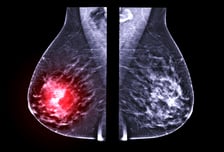

한국 여성이 폐경 이행기에 체질량 지수(BMI)에 따라 호르몬 변화와 유방 밀도가 달라지는데, 이게 유방암 발생 위험에 영향을 미칠 수 있다는 연구 결과가 발표됐다. 한국·일본 등 아시아 여성은 서구 여성보다 젊은 연령인 40대 후반에 유방암 발생이 정점을 보인다. 유방암은 여성호르몬에 영향을 받고, 유방 밀도가 높을수록 유방암이 생길 가능성이 커지는 것으로 알려졌다. 이에 성균관의대 강북삼성병원 헬스케어데이터센터 류승호, 코호트연구센터 장유수 교수, 장윤영 박사, 서울아산병원 가정의학과 조유선 교수 공동 연구팀은 폐경 이행기 여성 4737명을 평균 7년간 추적 관찰해 폐경 이행기 동안의 여성호르몬 변화와 유방 밀도 변화를 확인했다. 폐경 단계는 국제 표준 STRAW+10 기준에 따라 4단계로 분류했으며, 유방 밀도는 유방 촬영 영상을 자동분석 프로그램으로 정량화했다. 또한 체질량 지수는 저체중(<18.5), 정상체중(18.5-22.9), 과체중(23-24.9), 비만(≥25)의 4